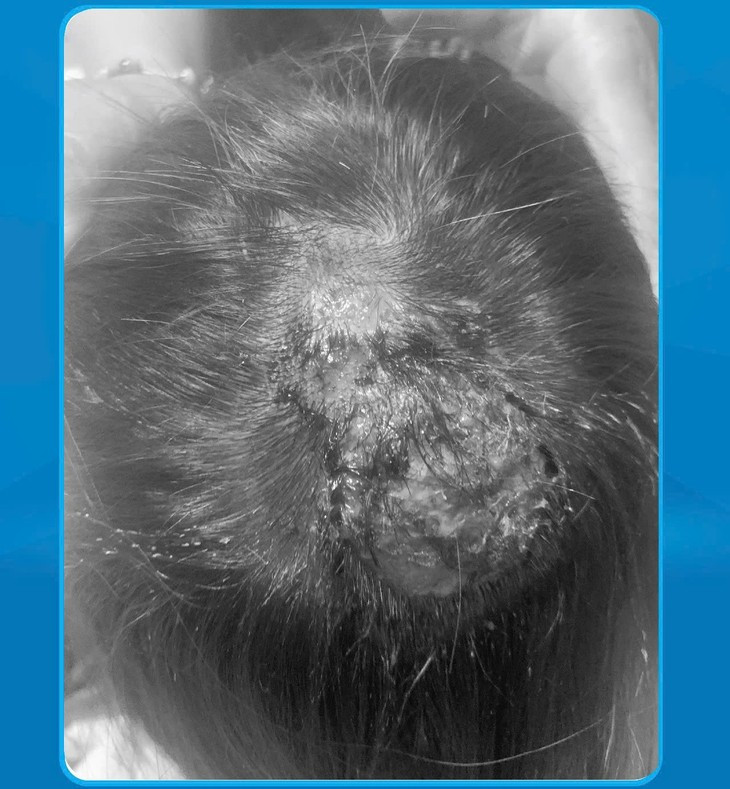

Tại Bệnh viện Đa khoa Hùng Vương (Phú Thọ), bệnh nhi được chẩn đoán: Đa ổ áp xe vùng chẩm do nấm hoại tử bội nhiễm dẫn đến hoại tử da đầu. Các ổ áp xe có kích thước từ 1cm đến 4x4cm, nhiều ổ đã vỡ mủ và đóng vảy.

| Hoại tử da đầu vì nấm - Ảnh BVCC |

Với tình trạng hoại tử da gây khuyết hổng phần mềm kích thước lớn lộ xương không có khả năng khâu trực tiếp, các bác sĩ đã khẩn trương thực hiện phẫu thuật chuyển vạt da để che phủ tổn thương, đảm bảo phục hồi không chỉ về mặt sức khỏe mà còn yếu tố thẩm mỹ, đặc biệt quan trọng với bệnh nhi gái.